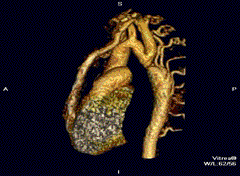

Aortic coarctation using different imaging techniques[10] -

Coarctation of the aorta -

Coarctation of the aorta

3D model of coarctation of aorta